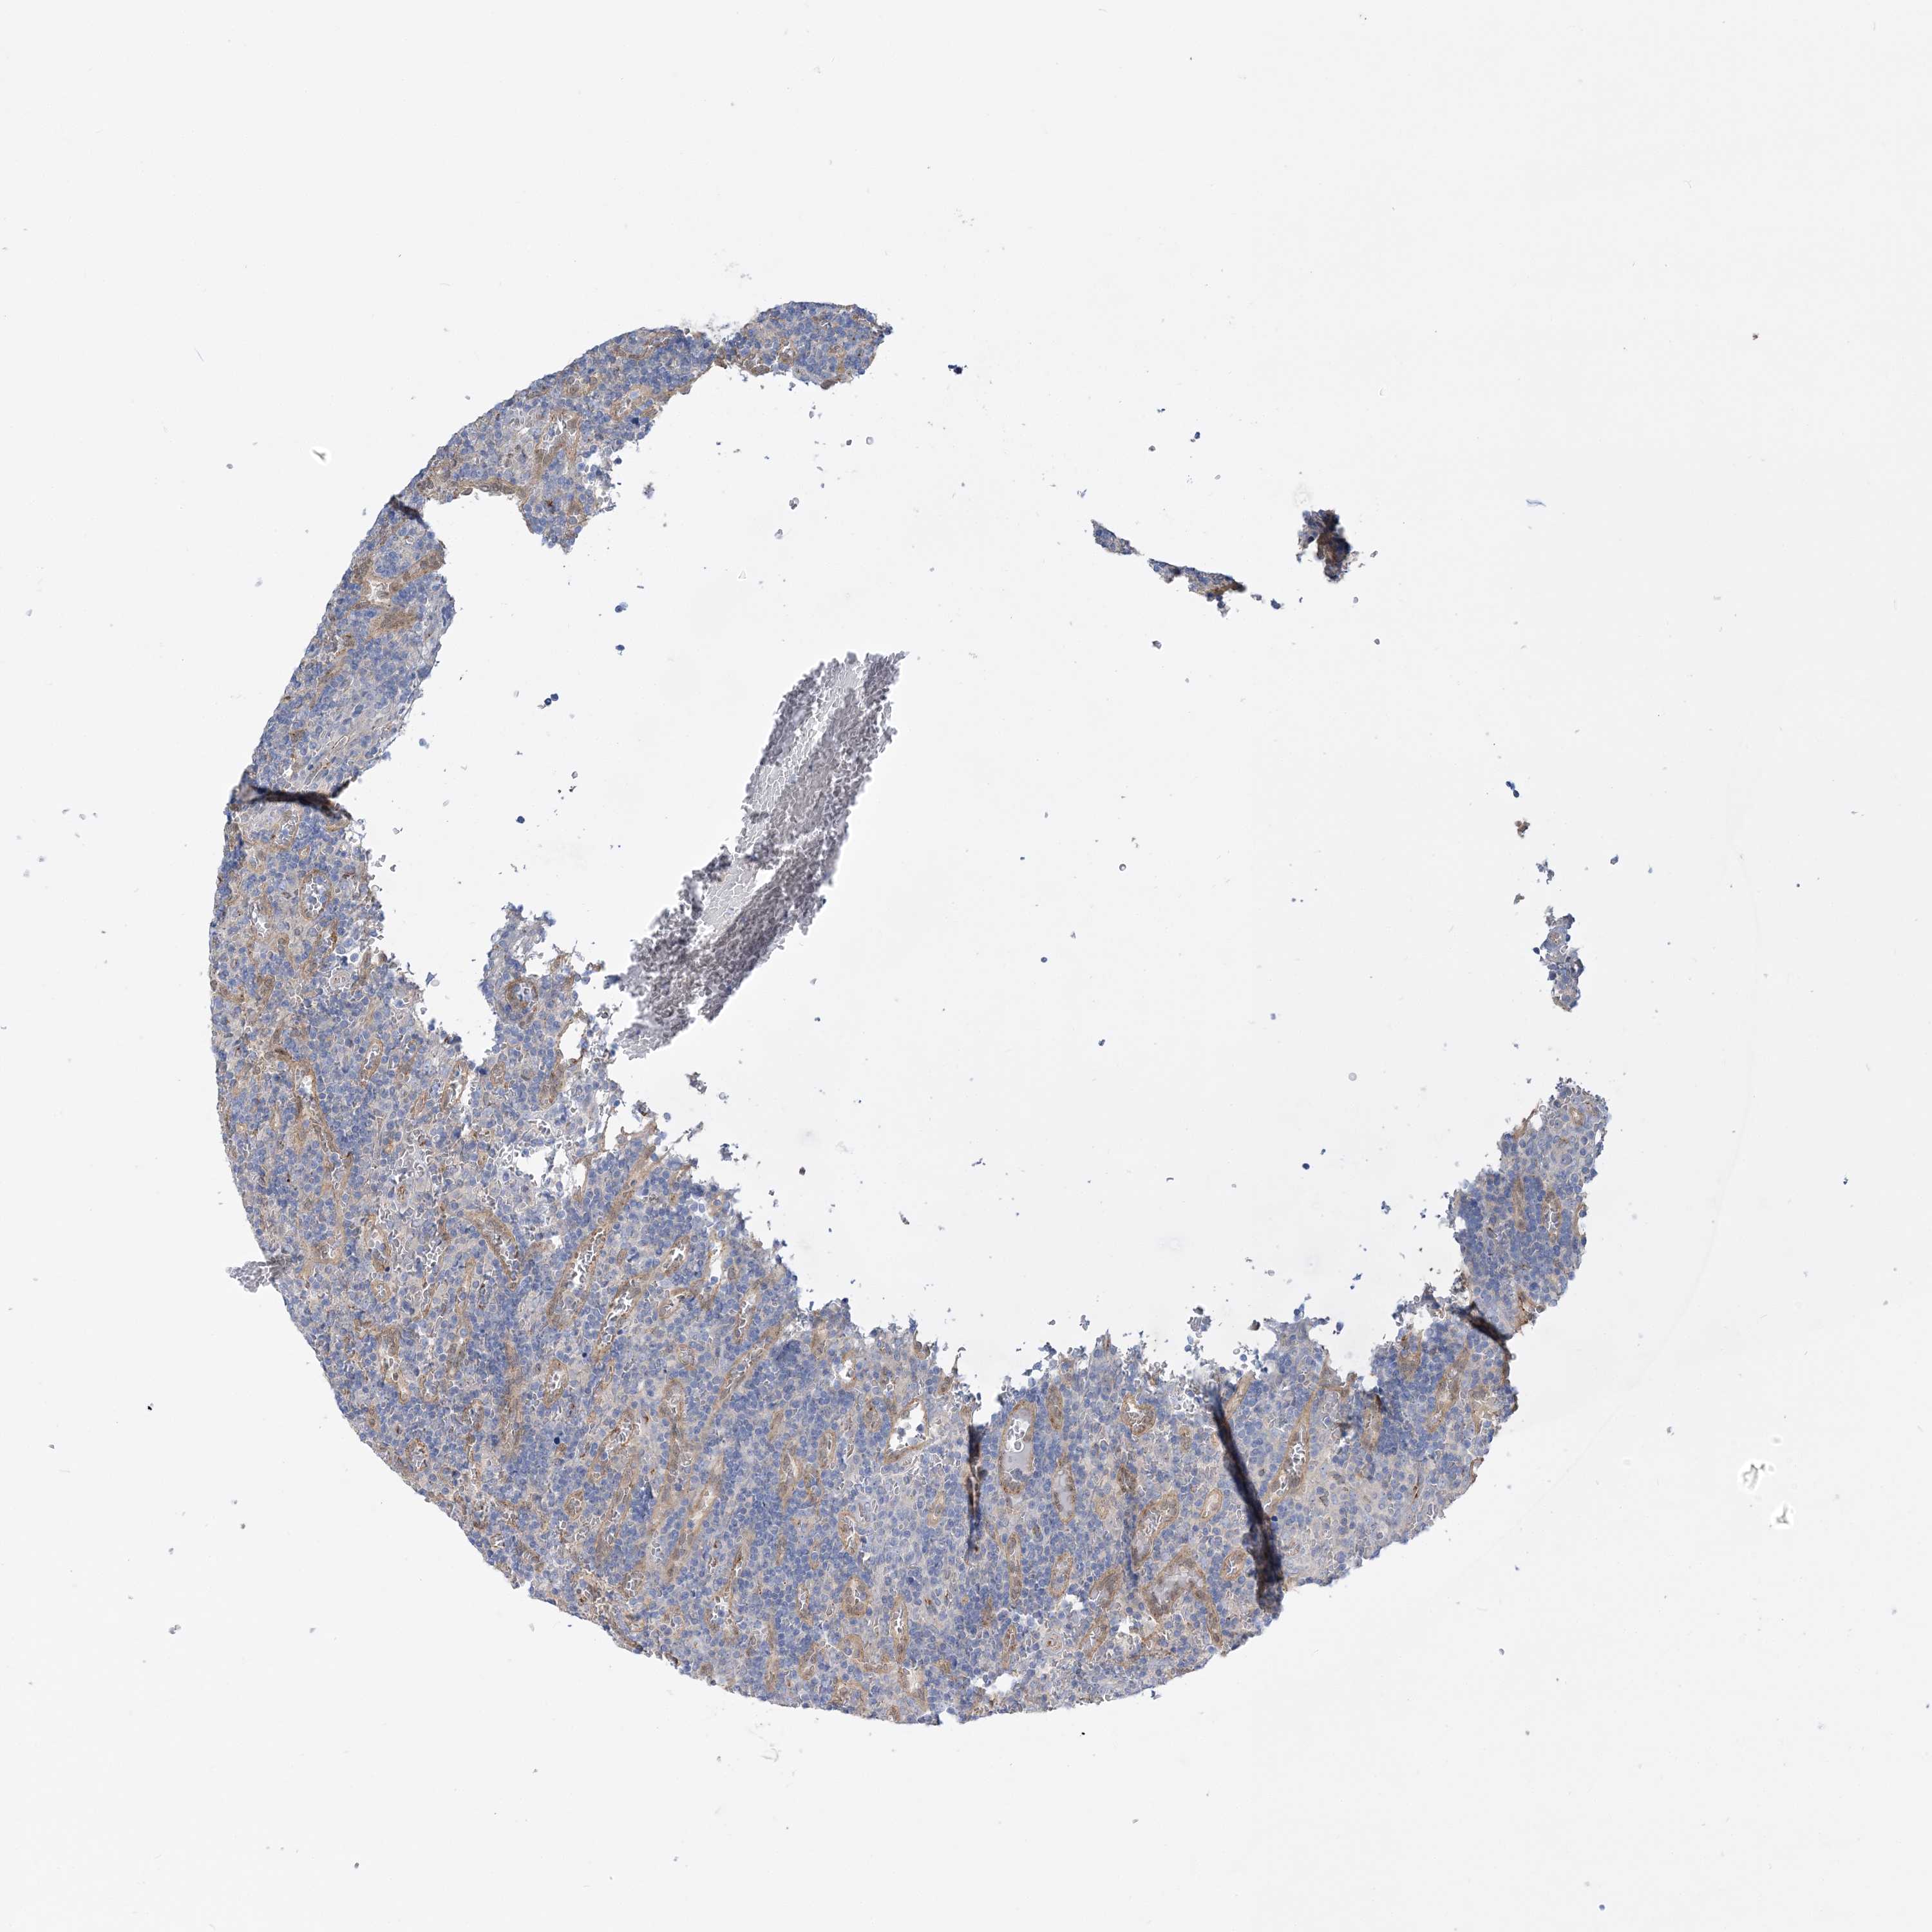

CANCER LYMPHOMA Show tissue menu

LYMPHOMA - Protein expressioni

A mouse-over function shows sample information and annotation data. Click on an image to view it in a full screen mode. Samples can be filtered based on level of antibody staining by selecting one or several of the following categories: high, medium, low and not detected. The assay and annotation is described here.

Each image is clickable and will lead to virtual microscopy that enables deeper exploration of all samples and also displays staining intensity scores, fraction scores and subcellular localization as well as patient and tissue information for each sample.

Antibody HPA036698

Antibody HPA036699

Hodgkin's disease, NOS

Malignant lymphoma, non-Hodgkin's type, High grade

Malignant lymphoma, non-Hodgkin's type, Low grade